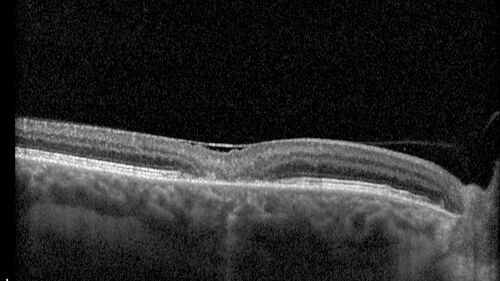

MacTel with foveal atrophy in both eyes

62 year old female with 20/50 OD, 20/40 OS.

MacTel with foveal atrophy OU